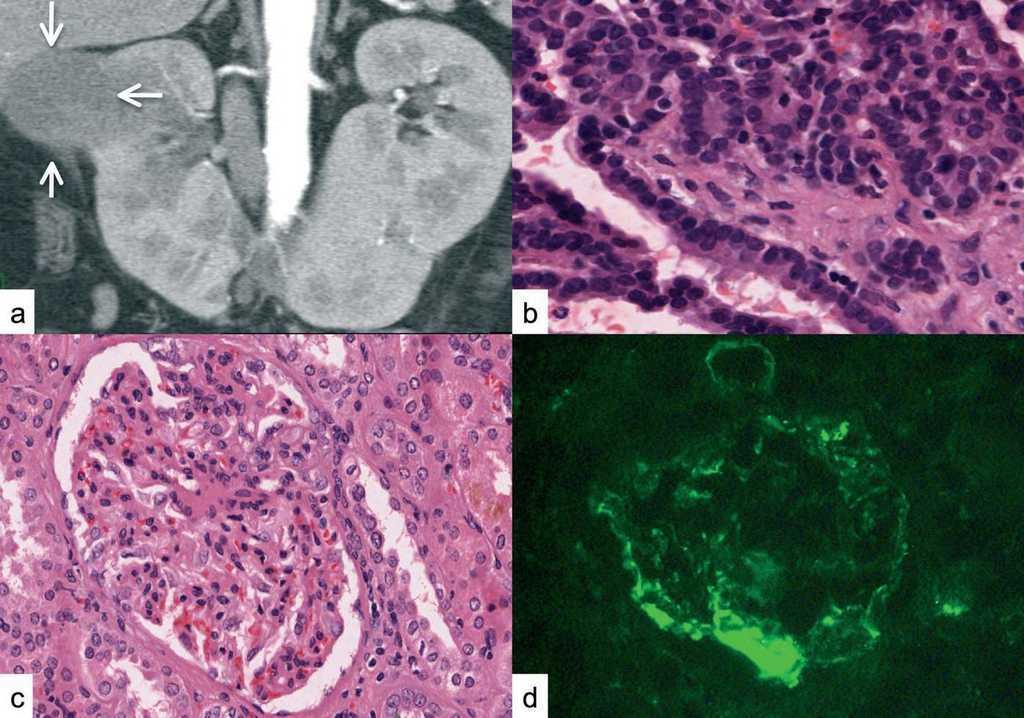

Una semana antes del ingreso (octubre de 2007), inicia un cuadro de edemas. En la analítica presentaba: proteinuria 18 g/24 h, albúmina sérica 2,1 g/dl e hiperlipemia, asociadas con microhematuria y creatinina sérica de 1,6 mg/dl. En la exploración: tensión arterial de 103/60 mmHg, índice de masa corporal (IMC) de 21 kg/m2 y edemas generalizados. Hemograma y estudio de coagulación normales. ANA, anti-ADN, ANCAS, anticuerpos anti-MBG, crioglobulinas, anticoagulante lúpico, anticuerpos anticardiolipina y anticuerpos antivirus de las hepatitis B y C y del virus de la inmunodeficiencia humana (VIH), negativos. La ecografía y la TC confirman la presencia de RH, con un tumor en el polo superior del riñón derecho (figura 1a). La ccistografía es normal. Se realiza una nefrectomía con exéresis del istmo inferior. En el postoperatorio, se producen sangrado local y fracaso renal agudo parcialmente recuperado (creatinina 3 mg/dl).

La pieza de nefrectomía mide 14 x 6 cm con un tumor de 4 x 4,5 cm. En el estudio microscópico, se confirma adenocarcinoma renal con patrón de células cromófobas y eosinófilas (figura 1b). La vena renal no se encontraba infiltrada.

El estudio con microscopio óptico de una cuña adyacente puso de manifiesto unos glomérulos aumentados de tamaño, algunos hialinizados. En los restantes, había aumento de matriz mesangial y colapso capilar con varias células espumosas, importante fibrosis intersticial e infiltración de células inflamatorias. En la inmunofluorescencia, se detectaron depósitos mesangiales y parietales de IgM y C3 con distribución segmentaria y focal (figura 1c y figura 1d).

Figura 1. a) TAC abdominal: riñón en herradura con masa en polo superior de riñón derecho (flechas), b) adenocarcinoma renal con células tumorales con patrón papilar, c) glomérulos grandes con engrosamiento de la pared capilar, d) depósitos mesangiales y parietales